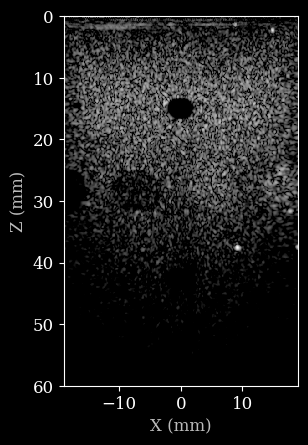

plot_data(image, dynamic_range, scan)

Now let’s construct a custom pipeline to process the data. We will use the zea.Pipeline

class and pass a list of operations to it. The operations will be executed in the order they are provided, and the output of each operation will be passed as input to the next operation as a dictionary. You can specify the input and output key for each operation, which for will be assumed to be data

by default. This also allows you to create complex branched pipelines, but we will keep it simple for

now. Note that pipelines can also be nested, which we will do for the beamforming stage. This allows us to use the zea.ops.PatchedGrid

pipeline to wrap the beamforming operations, resulting in a more memory efficient pipeline.